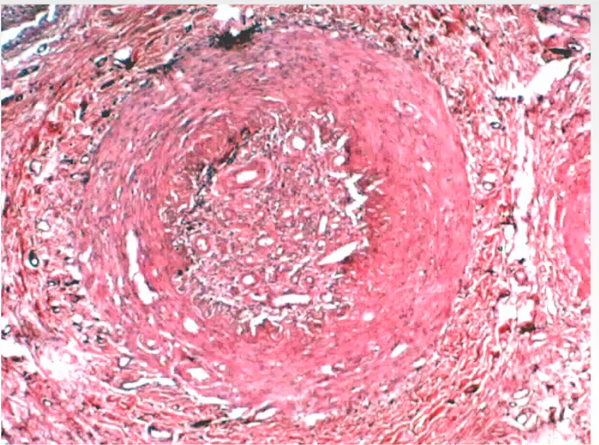

How do you check for atherosclerotic embolism

If you see cholestrol crystals in the center of the lumen of the vessel then they probably came from upstream, cholestrol clefts dont form in the center of the lumen, they form at the edges but they can get dislodged and travel downstream